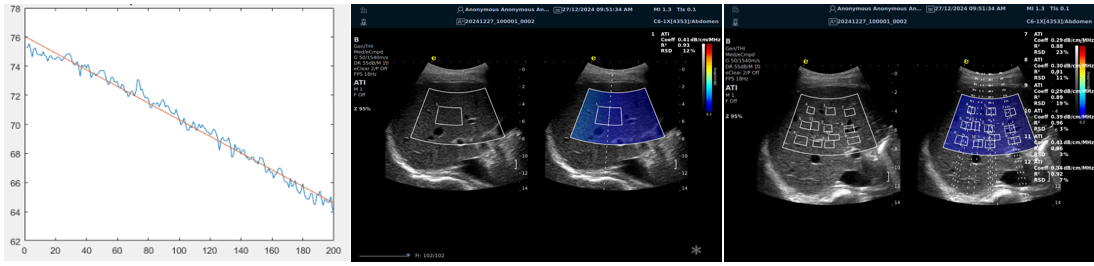

ATI高级声衰减成像

?独有的幅度损失的衰减方法ALA,准确性高,稳定性好,实时性好?业界唯一支持凸阵与线阵两种探头?支持多个取样框?提供两种显示单位

肌骨领域的应用

?肌腱炎症或损伤的评估?肌肉拉伤的定位?关节磨损或炎症的诊断?骨质疏松的早期发现和监测